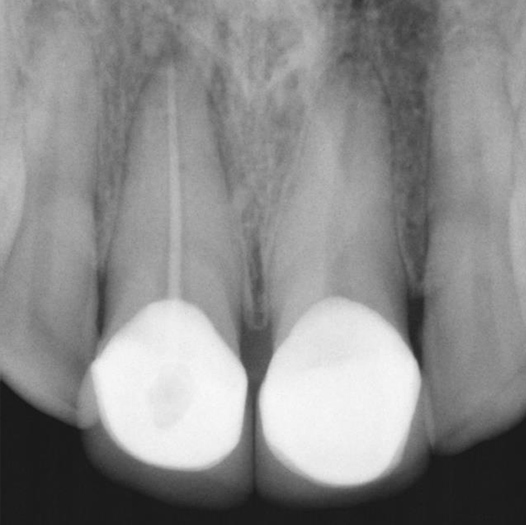

Before

Before Root Canal treatment